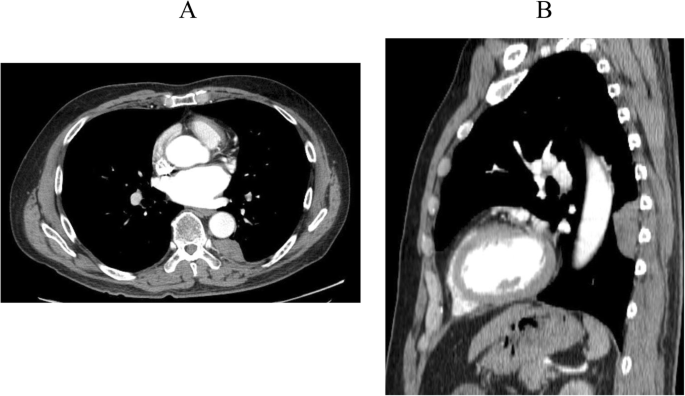

A 60-year-old man was admitted to our hospital for further examinations of an abnormal shadow found on a chest CT. A CT scan demonstrated a homogenous, sharply-circumscribed mass in the posterior mediastinum (Fig. 1). Additional file 1A (Video) showed preoperative DCR findings. Two points for measurements on the inspiratory frame of the dynamic-ventilation. One point was placed in the center of the targeted lesion (red point). The other point was the vertebra adjacent to the tumor (blue point). The software automatically tracked these two measuring points, and coordinates were recorded. The distance of the two points (Additional file 1B), movement in two directions (Additional file 1C) were not coincidence, which means no invasion or adhesion of the tumor to the chest wall.